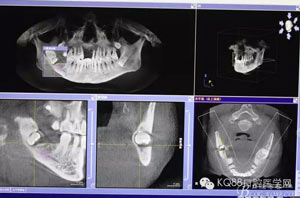

圖4.總體的CBCT影像: